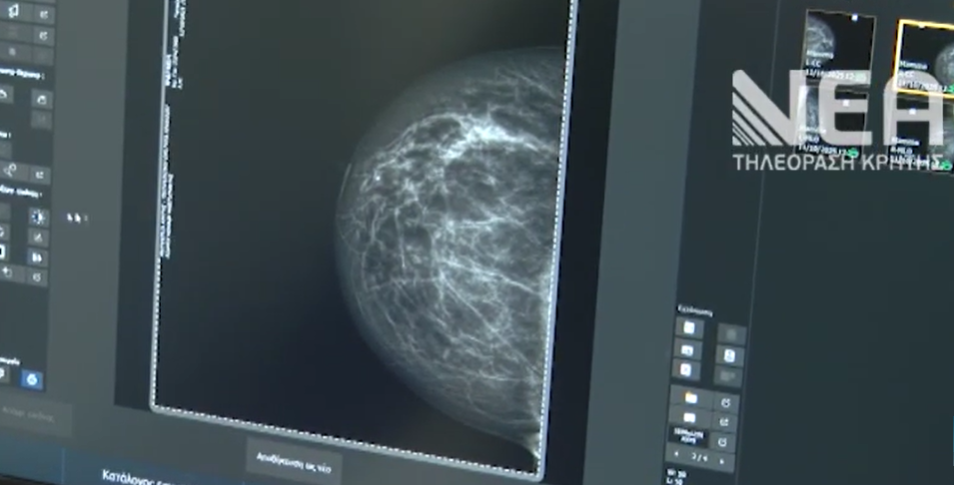

Κάθε χρόνο, περίπου 1 στις 8 γυναίκες στην Ελλάδα θα προσβληθεί από καρκίνο του μαστού, με τον αριθμό των νέων περιστατικών να ανέρχεται περίπου στις 4.500 ετησίως. Στις Στέρνες Ακρωτηρίου βρέθηκε για δύο ημέρες η Κινητή Μονάδα Μαστογραφίας στο πλαίσιο της εκστρατείας “Η πρόληψη είναι στάση ζωής ”, πραγματοποιώντας πάνω από 100 δωρεάν προληπτικούς ελέγχους. Την δράση διοργάνωσε η Ενορία Στερνών με την στήριξη της Περιφέρειας Κρήτη.